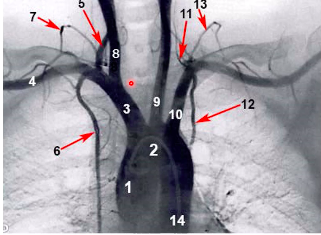

label 1-10 xox

what do the following supply?

desecribe the structure / layout of the posterior intercostal arteries (3)

- posterior intercostal arteries (3-12) come off at regular intervals from the descending aorta, except for the first two posterior intercostal arteries, which come from the costocervical trunk (branch that comes off subclavian arteries)

describe the layout of anterior intercostal arteries xo

- the anterior intercostal arteries are branches of internal thoracic arteries (which themselves come off the subclavians)

how do the anterior and posterior intercostal artieres connect? which line does this occur?

what happens if damage to one of anterior / posterior arteries occurs?

anterior and posterior intercostal artieres connect via anastomosis @ mid-clavicular line

most of the intercostal region is supplied by the posterior intercostal arteries

if damage to one of anterior / posterior IC arteries, the collateral circulation can supply the rest of the thoracic cage

what is difference between the anterior and posterior intercostal arteries?

anterior IC arteries: much larger superior branch AND a smaller collateral inferior branch

posterior IC arteries: only single artery all the way down